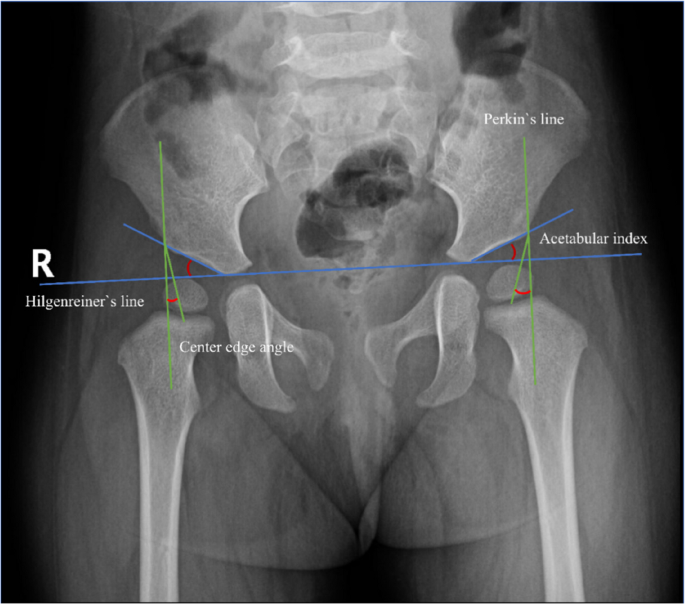

This research primarily investigates the impact of pictures angle variation on the measurement of the acetabular index (AI) and center-edge angle (CEA) in pediatric hip joints. AI is outlined because the angle between the road connecting the apexes of the bilateral Y-shaped cartilage (known as Hilgenreiner`s line) and the road drawn to the outer fringe of the acetabulum. CEA is measured utilizing Wiberg’s methodology of the CEA [9], which represents the angle between the road connecting the midpoint of the femoral head and the outer fringe of the acetabulum relative to the Perkin`s line (Fig. 4). Two skilled pediatric orthopedic surgeons measured the AI and CEA for every picture, repeating the measurements two weeks later. This was performed to evaluate each inter-observer and intra-observer reliability. The common of the 2 surgeons’ measurements was taken because the reference worth. Previous research documented measurement errors of AI and CEA have been 6° and 4° [12, 13], respectively. In this research, Measurement accuracy was outlined because the measurement error inside these clinically established thresholds. Changes under these validated thresholds have been thought-about clinically acceptable.

Method of measuring AI and CEA